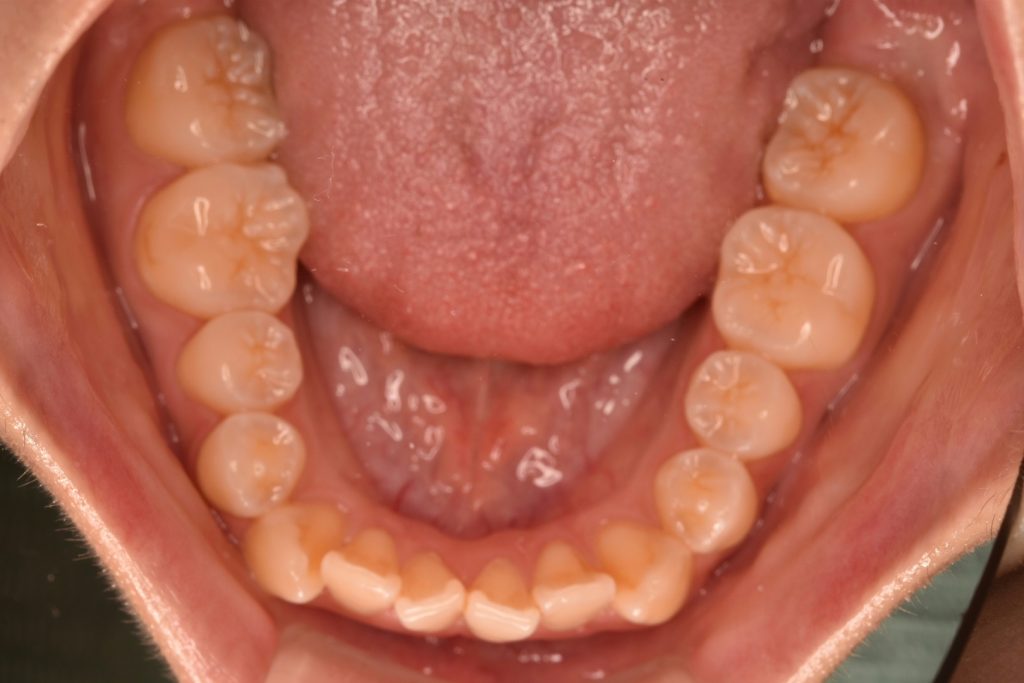

初診時

前歯が空いていて、奥歯でのみ噛んでいる状態です。ガタガタも認められます。